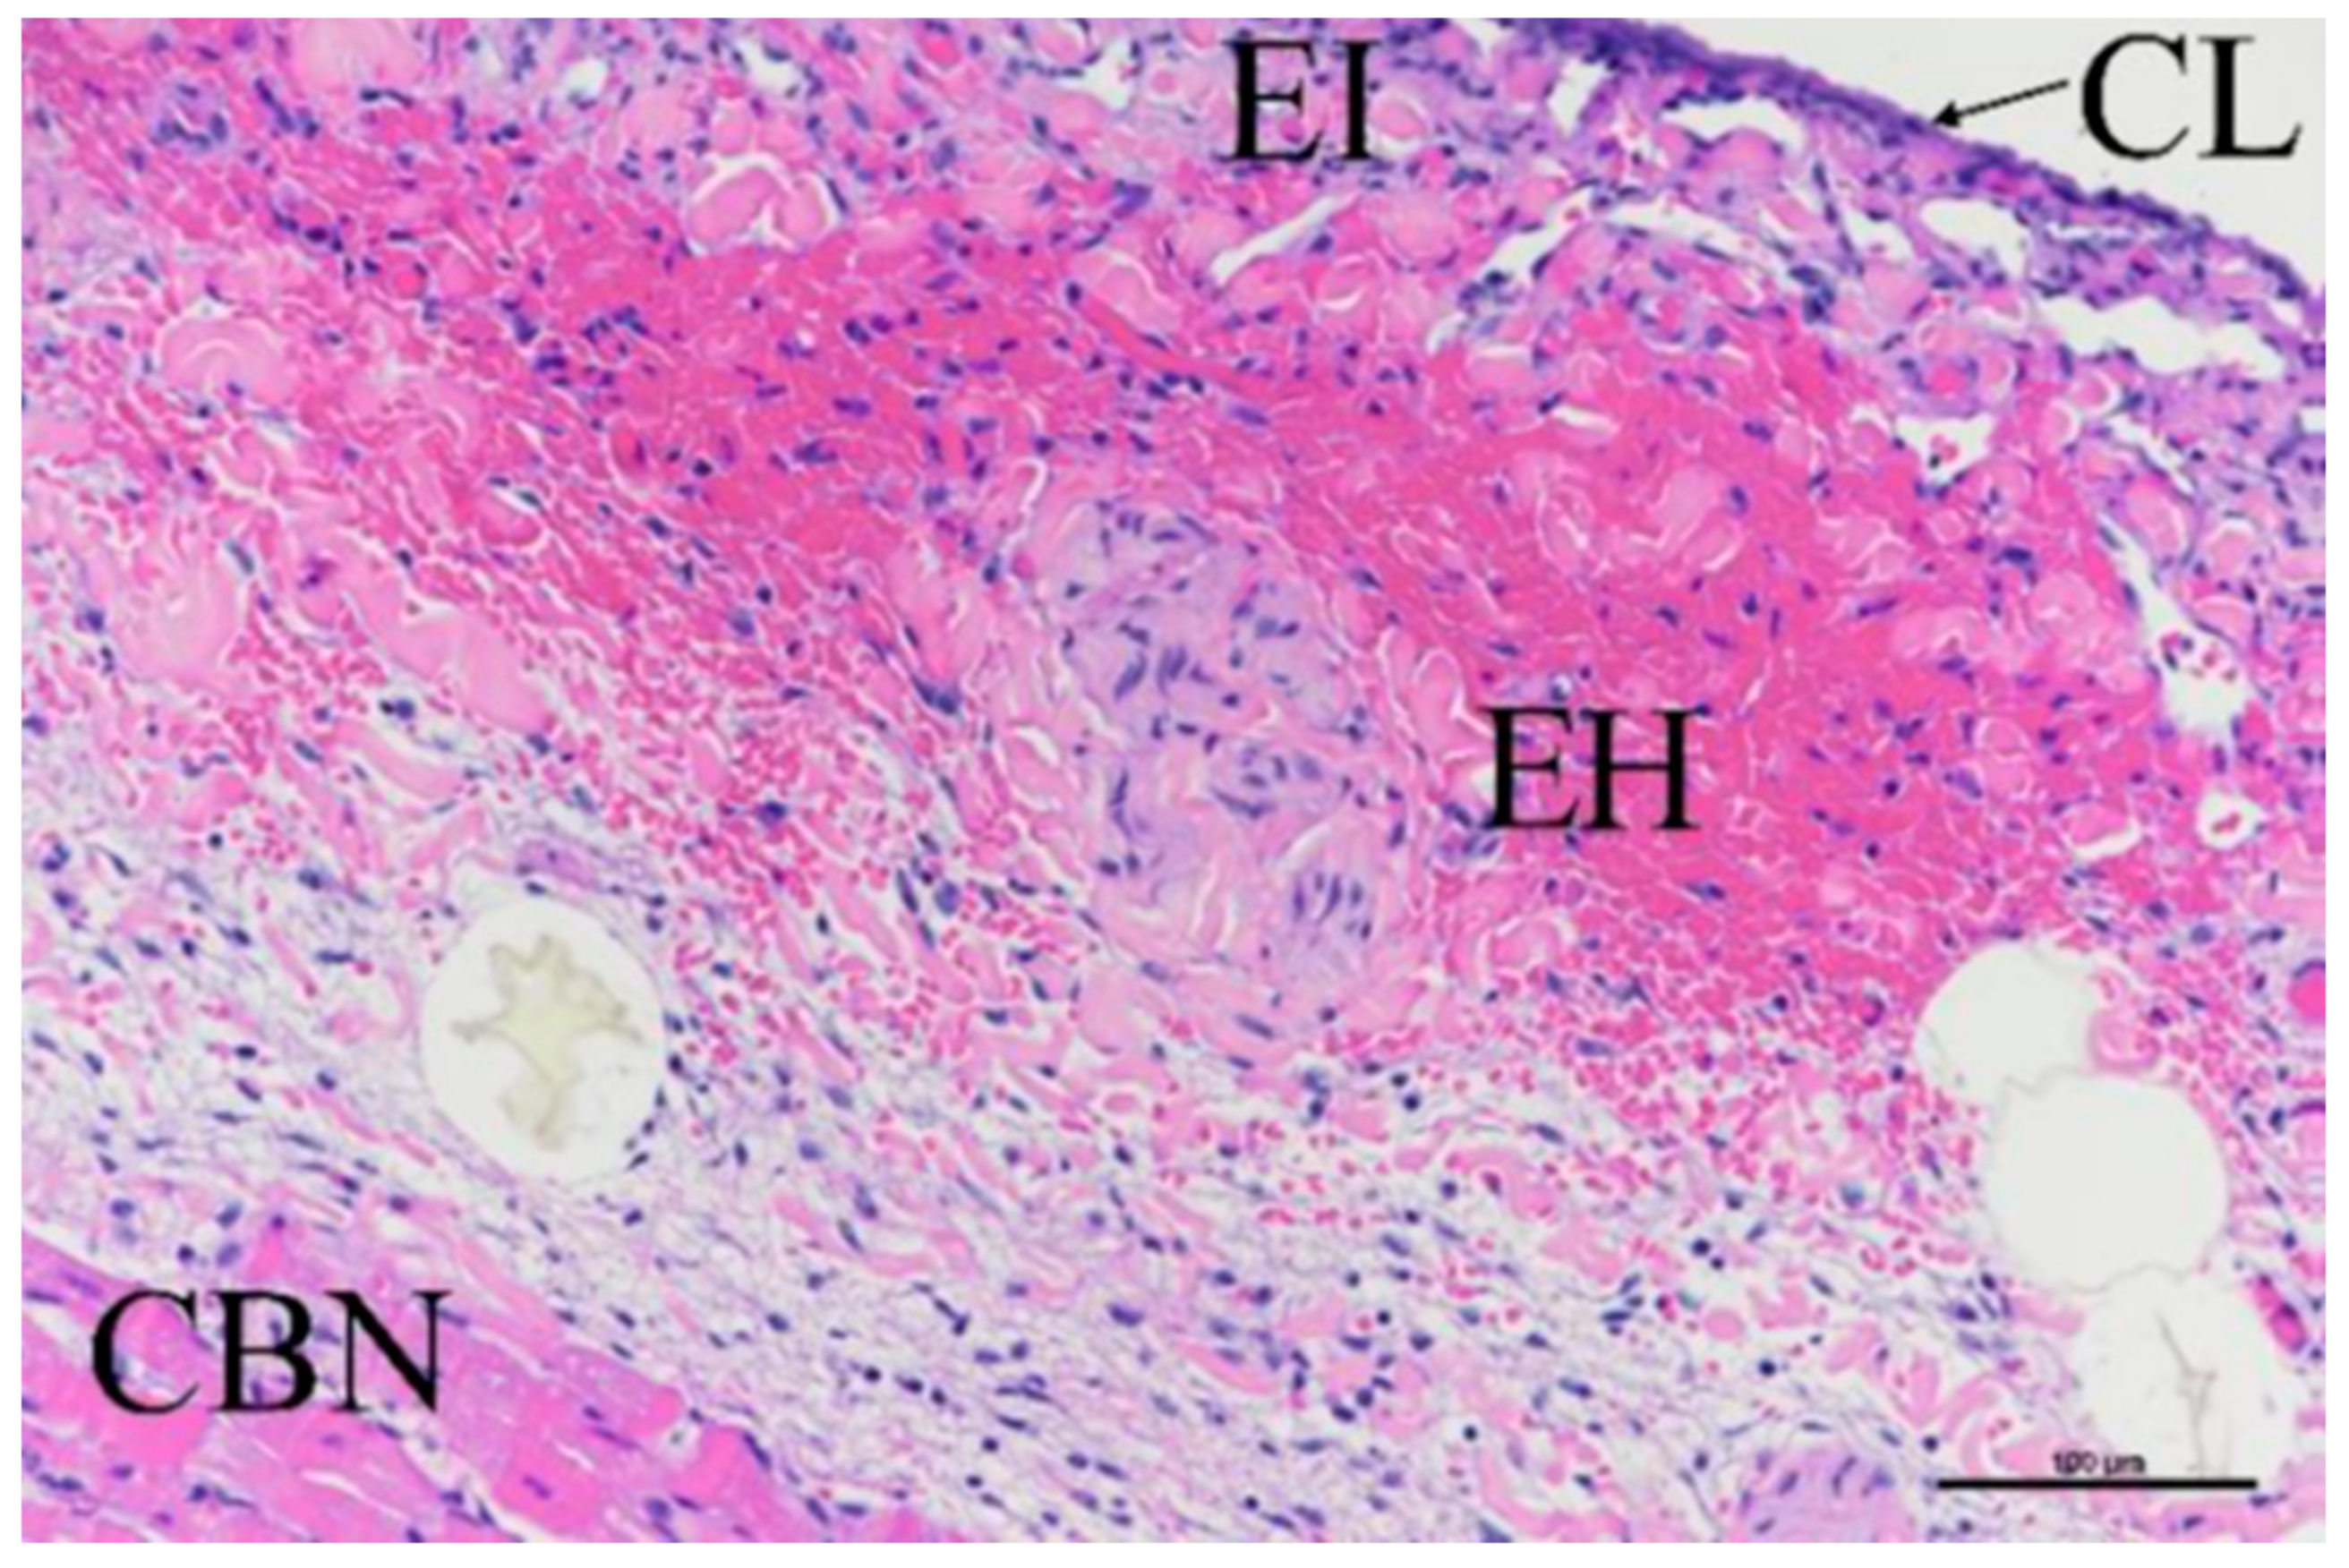

2.4. Histological Evaluation

3.3. Histologic Evaluation

3.4. Porcine Study—Catheter Access and Navigation